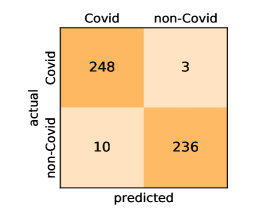

Here, we present and discuss the obtained results for detecting COVID-19 on the considered CT image datasets with different deep networks. We report the quantitative results along with the confusion matrices for every single architecture of the adopted networks.

On the SARS-CoV-2 CT dataset, ResNet101 achieves the best overall performance with respect to almost all evaluation metrics, with an average accuracy and F1-score of and , respectively. The model also achieves an average sensitivity rate of indicating that, on average, only two COVID-19 images are falsely predicted as negatives. It is also powerful enough to correctly identify all Non-COVID-19 cases with only one false positive resulting a specificity rate of . The highest sensitivity score of is achieved by the InceptionV3 model, where only one COVID-19 image is falsely predicted as negative on average. The SqueezeNet model obtains the lowest performance with respect to all evaluation metrics with a fairly acceptable average accuracy and sensitivity scores of and , respectively. Also the ShuffleNet architecture obtains satisfactory performance with approximately improvements on average for all metrics compared with SqueezeNet. Although the results obtained by these models are inferior compared with the rest of models, but they are more efficient. This matches their main objective of reducing the computational costs rather than improving their visual recognition abilities. The rest of models achieve competitive performance and very promising results with slight performance differences. Comparing the different variants of ResNet and DenseNet, we can see that the deeper variants from each architecture yield a slightly better performance. The deeper ResNet101 and ResNeXt101 show a marginal gain in performance compared with their shallower counterparts. The details about class-wise results for each model are summarized in the confusion matrices in Figure 9.